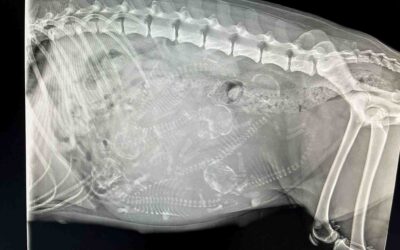

Nasz nowy dywan. Mikasa 58 dzień ciąży.

55 dzień ciąży. Piesełki Mikasy i Vigo